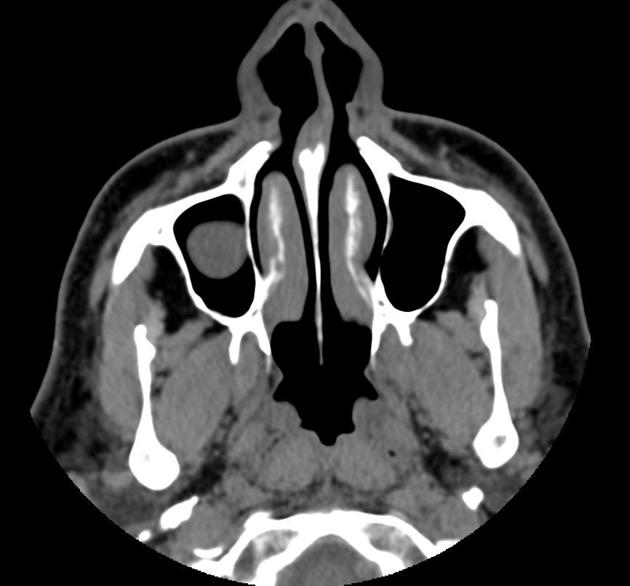

Sinus mucous retention cyst Radiology Case Radiopaedia

Product Name: Maxillary sinus retention cyst saleParanasal sinuses retention cysts Radiology Reference Article Radiopaedia sale, PDF Maxillary Sinus Retention Cysts Protruding Into the Inferior Meatus Semantic Scholar sale, Optimal timing of endoscopic sinus surgery for the retention cyst of maxillary sinus The Journal of Laryngology Otology Cambridge Core sale, What is a Maxillary Sinus Retention Cyst sale, Ruptured Maxillary Retention Cyst Cause of Unilateral Rhinorrhea after Trauma American Journal of Neuroradiology sale, Panoramic radiographs with images suggestive of a bilateral mucous. Download Scientific Diagram sale, Clinical and Experimental Otorhinolaryngology sale, Mucous retention cysts of maxillary sinus Radiology Case Radiopaedia sale, Ruptured Maxillary Retention Cyst Cause of Unilateral Rhinorrhea after Trauma American Journal of Neuroradiology sale, Unusually large radicular cyst presenting in the maxillary sinus BMJ Case Reports sale, Sphenoid Sinus Mucous Retention Cyst vs. Mucocele correction Slide 5 sale, Maxillary sinus mucous retention cyst removal thoughts sale, Are mucous retention cysts and pseudocysts in the maxillary sinus a risk factor for dental implants A systematic review. Abstract Europe PMC sale, What does left maxillary sinus small retention cyst noted mean in radiology Quora sale, Paranasal sinuses retention cysts Radiology Reference Article Radiopaedia sale, Combined vascular malformation and retention cyst in the maxillary sinus ScienceDirect sale, Optimal timing of endoscopic sinus surgery for the retention cyst of maxillary sinus The Journal of Laryngology Otology Cambridge Core sale, Mucucoele of the maxillary sinus and the eye Eye sale, Endoscopic sinus surgery for maxillary sinus mucoceles Head Face Medicine Full Text sale, Surgical outcomes between two endoscopic approaches for maxillary cysts ScienceDirect sale, 330KB 2001 null null null null 3 3 2003 null 5wIhQ6 k1nu nM sale, Clear Lake Medical Center ENT Mucous retention cysts develop in the lining sinuses. Unless they block drainage of your sinuses these cysts typically do not cause pain infection or breathing issues sale, Frequency and characteristics of retention cysts in the maxillary sinus in a Turkish patient population international journal of stomatology occlusion medicine sale, Sleep Apnea Sleep and Brain sale, Sinus mucous retention cyst Radiology Case Radiopaedia sale, Endoscopic sinus surgery for maxillary sinus mucoceles Head Face Medicine Full Text sale, Automatic diagnosis of retention pseudocyst in the maxillary sinus on panoramic radiographs using a convolutional neural network algorithm Scientific Reports sale, Imaging in Sinonasal Disorders IntechOpen sale, Mucous retention pseudocyst MRP of the right maxillary sinus on. Download Scientific Diagram sale, Severe facial pain and removal of maxillary sinus mucous retention cyst BMJ Case Reports sale, Maxillary Sinus Mucocele sale, Association between the seasonal changes and mucous retention cyst of maxillary antrum in cone beam computed tomography images in a sample population of Isfahan Iran Semantic Scholar sale, Symptomatic mucous retention cysts of the maxillary sinus case report sale, Clinical evaluation of sinus bone graft in patients with mucous retention cyst Maxillofacial Plastic and Reconstructive Surgery Full Text sale, Clinical evaluation of sinus bone graft in patients with mucous retention cyst Maxillofacial Plastic and Reconstructive Surgery Full Text sale.